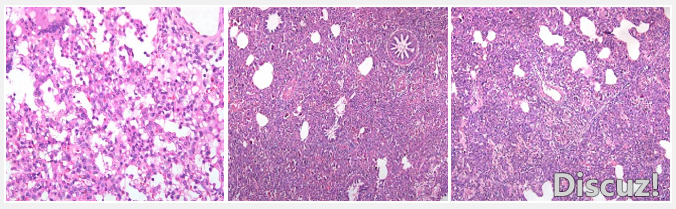

藍耳病,動脈炎屬,病毒1991年被分離。即使在科技迅速發展的今天,藍耳病仍然能帶來無法估量的損失。 發病機理-肺巨噬系統的重要性 作為免疫抑制疾病的代表,藍耳病毒主要是攻擊全身的巨噬細胞系統。巨噬細胞系統 ...